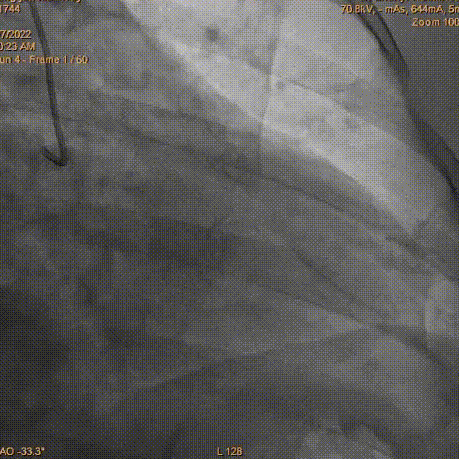

冠脉造影

LCA大致正常

RCA迂曲远段中重度狭窄